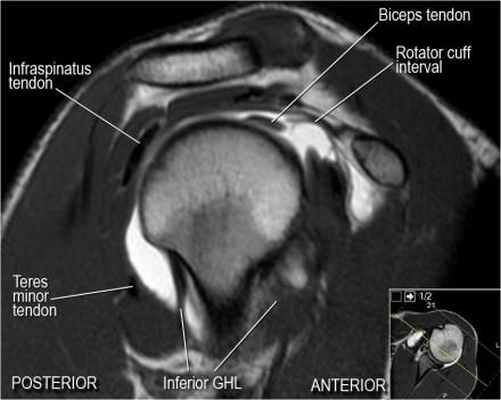

Изображение передних отделов плечевого сустава.

Сухожилие подлопаточной мышцы прикрепляется как к малому бугорку, так и к большому бугорку, давая поддержку длинной головке двуглавой мышцы в борозде двуглавой мышцы. Вывих длинной головки двуглавой мышцы плеча неизбежно приведет к разрыву части подлопаточной сухожилия. Манжета вращателей плеча состоит из сухожилий подлопаточной, надостной, подостная и малой круглой мышц.

Изображение задних отделов плечевого сустава.

Отображены надостная, подостная и малая круглая мышцы и их сухожилия. Все они прикрепляются к большому бугорку плечевой кости. Сухожилия и мышцы манжеты вращателей участвуют в стабилизации плечевого сустава во время движения. Без манжеты вращателей головка плечевой кости частично сместилась бы из суставной впадины, уменьшив силу отведения дельтовидной мышцы (мышцы вращательной манжеты координирует усилия дельтовидной мышцы). Повреждение манжеты вращателей может привести к смещению головки плечевой кости кверху, в результате вызвая высокое стояние головки плечевой кости.